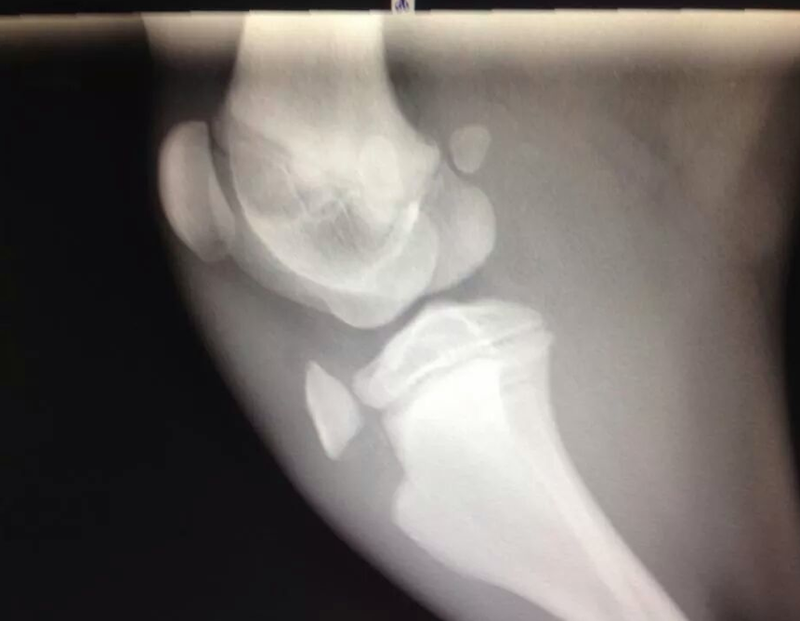

Please look below at all these x-rays from last years random friend’s injuries ( and these are without even searching as these happen all the time). If it is not a growth plate , it is a neck, back, wrist, hock, ribs or any large bones for that matter. One of the most common example is when a small piece of the knee joint splits, which end up in a 2-3000€ surgery. I do not see much point in taking such a huge risk, so don’t run adults and pups! Period!

Here is the proof! More info after the pictures!

• The diagrams below show the different type of fractures (the blue line represents the soft growth plate tissue, the red line represents the fracture line, and the speckled red line is a crushed growth plate).

• Type 3 – elbow (distal humerus)

• Type 4 – elbow (distal humerus)

• Type 5 – 1. wrist or carpus (distal ulna or the distal radius less commonly), this results in an angular limb deformity); 2. ankle or hock (distal tibia)